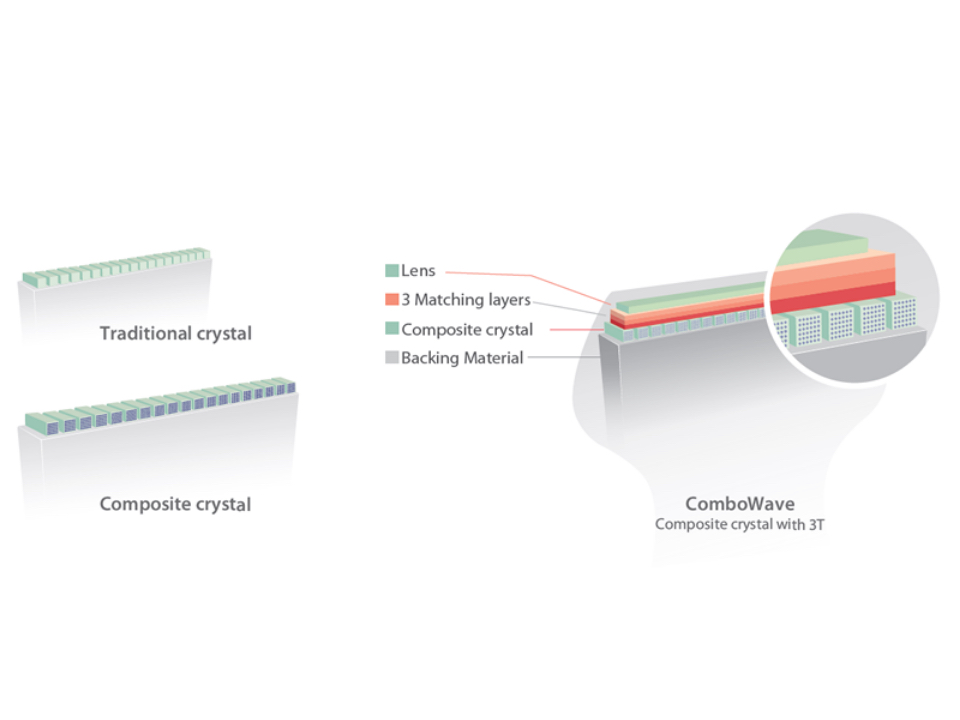

eXpress Clarity

More clarity at hand

To achieve excellent images with minimal effort is always the highest clinical priority and Mindray's endless pursuit. With continuous innovation of imaging and transducer technologies, X-Insight delivers express clarity as soon as the transducer touches the body.